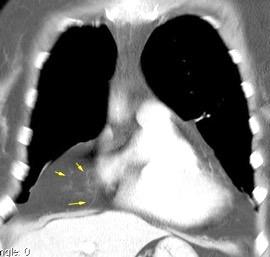

31. ENFERMEDAD TORACOABDOMINAL. TUMOR

Nódulos pulmonares múltiples. (flechas verdes). Masas paratraqueales. (flechas amarillas). Dudoso ensanchamiento retrocrural (flechas negras). sigue….

Ttawfik A et al. Trans-diaphragmatic Pathologies: Anatomical Background and Spread of Disease on cross-sectional Imaging. Current Problems in Diagnostic Radiology. 2021.

T. mixto de células germinales del testículo

izquierdo Metástasis pulmonares. (flechas verdes). Ganglios paratraqueales. (flechas amarillas). Ganglios retroperitoneales (flechas negras)

Tawfik A et al. Trans-diaphragmatic Pathologies: Anatomical Background and Spread of Disease on cross-sectional Imaging. Current Problems in Diagnostic Radiology. 2021.